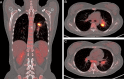

Background: Sepsis is a life-threatening condition caused by a dysfunctional response to infection from the host. Septic shock, a subset of sepsis, caused by Talaromyces marneffei infection (talaromycosis) has rarely been reported. Owing to its slow culture and low yield, talaromycosis is typically misdiagnosed in HIV-negative patients as other infections, such as tuberculosis, bacterial pneumonia, and lung cancer, especially in non-endemic regions. Early and accurate diagnosis as well as efficient treatment options are required to improve prognosis.

Method: A 30-year-old HIV-negative Chinese woman from a non-endemic area of T. marneffei was initially misdiagnosed with tuberculosis. She had a poor response to anti-tuberculosis treatment. On July 16, 2022, she was admitted to our hospital; the patient developed septic shock on the third day after hospitalization and was ultimately diagnosed with talaromycosis via metagenomic next-generation sequencing (mNGS).